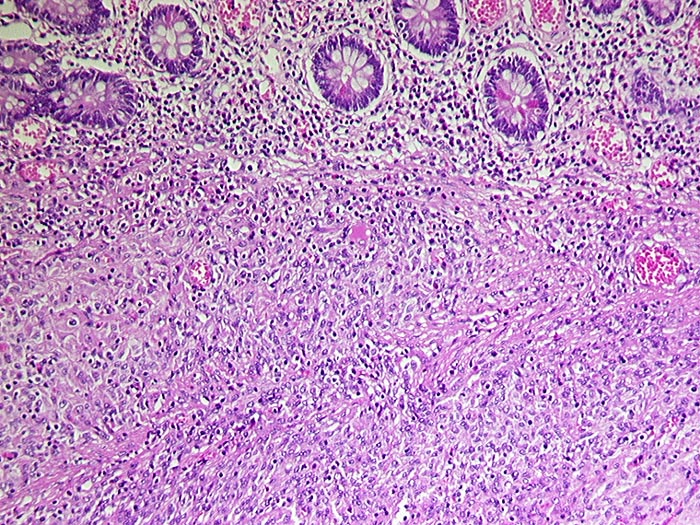

Makroskopisch imponieren kleine Tumoren als peritoneale, intramurale oder submuköse Knoten. Grössere Tumoren wölben sich oft vor und können ulzerieren. Die Schnittfläche ist weisslich und kann Einblutungen, Zysten, Fibroseareale oder Nekrosen aufweisen. Histologisch werden Spindelzelltyp (70%), Epitheloidzelltyp (20%) oder gemischtzelliger Typ (10%) unterschieden. Der histologische Subtyp scheint keinen Zusammenhang mit zugrundeliegender Mutation, Therapieansprechen und Prognose zu haben. Gelegentlich sind vor allem die kleineren Tumoren zellarm und kollagenreich.

• Der Tumor besteht aus längs und quer getroffenen Faszikeln spindelförmiger Tumorzellen, welche an glatte Muskelzellen oder Schwannzellen erinnern.

• Herdförmig pseudozystische Auflockerung des Tumorgewebes.